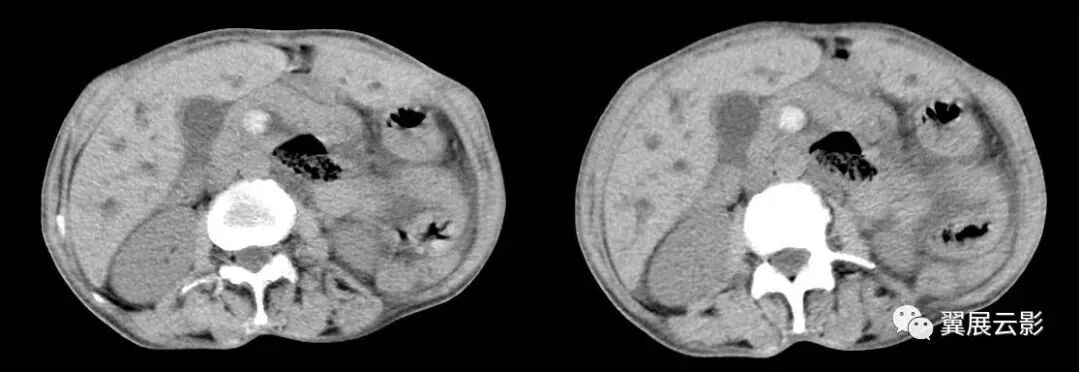

下图肠扭转病例:

16、漩涡征

在CT扫描时,多个条带状影围绕一个中心结构呈旋涡状排列,形成一软组织团块影。该征象高度提示小肠扭转时输入和输出肠管围绕一固定梗阻点旋转,并导致肠系膜绕轴旋转,是肠扭转的特异性征象,该征象包括肠管"漩涡征”及肠系膜血管“旋涡征”两个方面。当扭转小肠的输入襻和输出襻围绕着固定的梗阻点旋转时,肠系膜也随之沿旋转轴扭曲并紧密缠绕在肠襻之间,这些扭曲的肠襻和肠系膜血管分支形成了旋涡征中软组织密度的飘带状影,其背景是由肠系膜脂肪形成的低密度,由此形成了类似于气象图上旋风图样的外观,称为漩涡征。

当CT扫描与小肠的扭转轴相垂直时,漩涡征更清楚。肠扭转是一段肠袢沿其系膜长轴旋转而造成的闭袢型肠梗阻,同时肠系膜血管受压,也是绞窄性肠梗阻。常常是因为肠袢及其系膜过长,系膜根部附着处过窄或粘连收缩靠拢等解剖上的因素,并因肠内容重量骤增,肠管动力异常,以及突然改变体位等诱发因素而引起。肠扭转部分在其系膜根部,以顺时针方向旋转为多见,扭转程度轻者在360度以下,严重的可达2-3转。常见的肠扭转有部分小肠、全部小肠和乙状结肠扭转。

肠扭转时相应的肠系膜血管发生旋转,在CT图像中出现旋涡状改变通常称为“漩涡征”,表现形式有以下三种:肠管漩涡、肠系膜漩涡及以肠系膜血管为主的漩涡。因大部分病例肠系膜及系膜血管走行较复杂多不在一个平面上显示,因此肠系膜血管漩涡征以增强轴位CT 观察较好。 肠扭转后供给肠管血供的肠系膜血管发生扭曲,肠道血供障碍,肠管缺血缺氧而坏死形成绞窄性肠梗阻。因此,必须尽快准确判断患者的病情以选择哪些适合非手术治疗,哪些需要尽快手术探查。CT在判断肠梗阻患者中的作用,其敏感性达到83%,特异性为93%,准确率为91%。 小肠扭转虽然少见,但却是威胁生命的外科急症。

急腹症中的肠扭转、肠粘连、内抓疝等在很多情况下肠系膜及其血管同时发生旋转,并在CT图中显示,只要出现旋涡状改变,都可称之为漩涡征。漩涡征表现可有以下形式:肠管漩涡,肠管漩涡必有水肿系膜伴随,才能将肠管显示,多为静脉,可分为主干或分盘,前者常是扩张的肠系膜r静脉( SMV)围绕肠系膜上动脉(SMA)旋转后者系膜静脉分支构成漩涡状。Fisher所描述的CT上出现的漩涡征一个肠扭转的病例,该例涡轮的中心是肠系膜上动脉,涡轮样的外观是由环绕的扭曲肠襻所形成。Fishe提出漩涡征以后的文章中,许多作者描述了肠扭转的不同形式。Shaff等将漩涡征的定义延伸到乙状结肠扭转,此处漩涡征中的涡轮是由输入襻和输出襻所形成,中心部分由麻花状扭曲的肠管和肠系膜所构成,其指出涡轮的紧密度与肠扭转的程度成正比。Frank等提出漩涡征也可出现在自肠扭转,此处涡轮的构成包含了扭曲的肠系膜,塌陷的盲肠以及末端回肠襻。扩张的肠段在漩涡征出现处突然中止,高度提示肠扭转,且多为急性发生或者提示液体流入或分泌减少。

李文华等指出,漩涡征出现的位置有可能提供引起漩涡的病因。上腹部出现漩涡征,肠管又固定于定位置者,要考虑是否并发于内疝,如小网膜囊内疝、十二指肠旁疝等,应注意识别其解剖关系;中腹部出现漩涡征,多为单纯小肠扭转,而下腹部出现漩涡征,可能与乙状结肠扭转有关。 CT上漩涡征的出现能够提示肠扭转的发生,但是如果扫描平面与扭转轴不相垂直的话,漩涡征可能显示得不明显,其他有关小肠扭转的CT征象也有文献描述,比如扩张肠襻的放射状分布或U形结构,或者在扭转处肠管的纵切面形成的三角状或逐渐变细,上述这些CT征象在小肠闭襻性肠梗阻也可以观察到,依照闭塞段的长度、肠管扩张的程度、闭襻的位置方向以及CT扫描时切面的相对位置不同,显示也有所差异。 Blake和Mendelson报道部分手术如结肠部分切除术后患者,出现漩漏征并不具有特异性。尽管这些下术可能使肠管及肠最膜旋转述180度,但极少出现360度或更大角度旋转形成的漩转形成的漩涡征,因此在这些术后患者中出现漩涡征时,肠扭转仍然是一个排除性诊断。 总之.漩涡征的出现高度提示小肠扭转.但需要注意排除闭襻性肠梗阻。